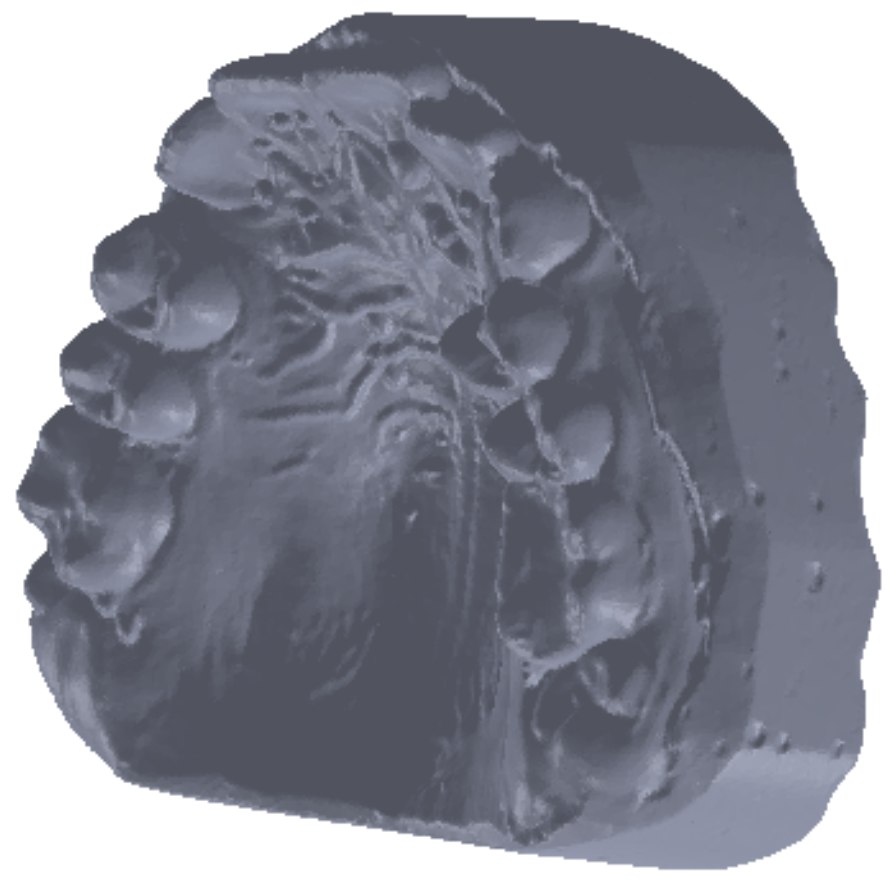

To obtain the final model, 30 successive scans were performed. Then, we obtained the final model of the scan operation. Figure 5 shows the common point cloud of the upper and lower images, which represents the raw, unprocessed model of the scanned maxillary.

Figure 5. Scanned image of the maxillary arch.